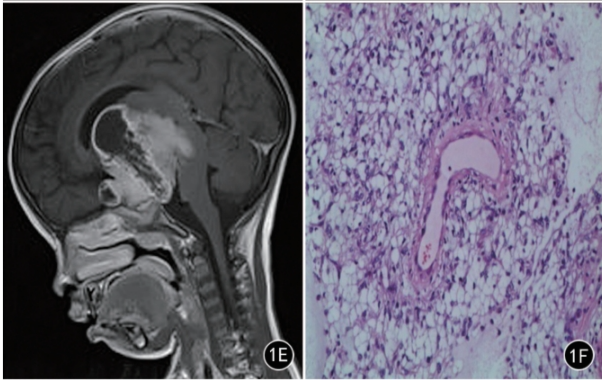

06e7657145437959301502d07fb2d30e.png

肿瘤细胞围绕血管生长是PMA的典型形态。

病理结果:毛细胞黏液样星形细胞瘤(Pilomyxoid astrocytoma,PMA)

8b69de51e3791866c2f82907dfecac36.png

A.肿瘤在T1上呈低信号

B.肿瘤在T2上成均匀高信号,侵犯视交叉和视束

C.T2 FLAIR上成稍高信号,肿瘤侵犯丘脑和基底节区

D.增强后明显强化

E.肿瘤内血管明显增生,肿瘤细胞常围绕血管呈血管中心性排列